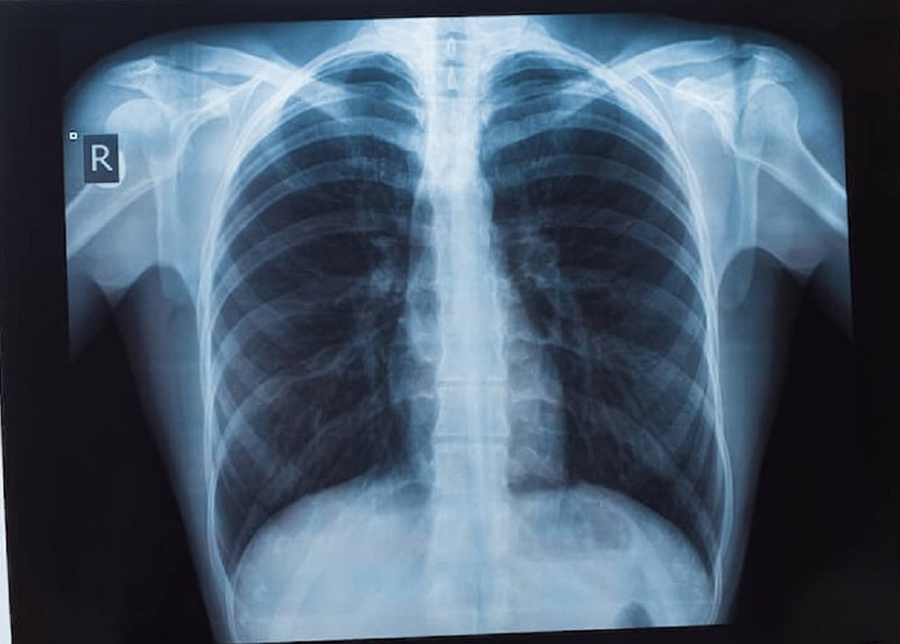

รศ.นพ.ศิระ เลาหทัย ศัลยแพทย์ทรวงอกจากศูนย์ผ่าตัดส่องกล้อง โรงพยาบาลวชิรพยาบาล กล่าวว่า มีคำถามยอดฮิตที่ว่า “เจอจุดที่ปอด (lung nodule) มีโอกาสเป็นมะเร็งกี่เปอร์เซ็นต์?” นั้นหลายครั้งที่เราไปตรวจสุขภาพแล้วพบเจอฝ้าขาว เมื่ออ่านผลรังสีวินิจฉัยพบเจอความผิดปกติในฟิล์มเอกซเรย์ปอด ทั้ง ๆ ที่เรายังไม่มีอาการผิดปกติใด ๆ เลย สิ่งที่สำคัญที่สุด ก็คืออย่าเพิ่งตกใจ เราต้องหาสาเหตุของจุดที่เกิดขึ้นมีจริงหรือไม่ โดยวิธีการที่หาสาเหตุที่ดีที่สุดคือ การทำเอกซเรย์คอมพิวเตอร์ (CT scan) แต่ไม่ควรที่จะทำเอกซเรย์ซ้ำ เพราะไม่เกิดประโยชน์ เนื่องจากการทำฟิล์มเปรียบเสมือนการถ่ายภาพ 2 มิติ เห็นแค่ด้านหน้า-หลัง ส่งผลทำให้เกิดผลภาพลวงได้บ่อย เปรียบเทียบกับการทำเอกซเรย์คอมพิวเตอร์เห็นรายละเอียด เป็นลักษณะของก้อนเนื้อว่าสงสัยมะเร็งหรือไม่ รวมทั้งมีจริงหรือไม่ หากการทำเอกซเรย์คอมพิวเตอร์ CT scan ไม่มีจุดหรือไม่พบจุด บางที่สิ่งที่เราเห็นจากฟิล์ม คือเงาที่ซ้อนทับกัน เนื่องจากมุมภาพ กรณีนี้มั่นใจได้ ว่าไม่มีอะไร ใช้ชีวิตปกติ ติดตามตรวจสุขภาพประจำปี ในทางกลับกัน เมื่อใดหากเราได้ทำเอกซเรย์คอมพิวเตอร์แล้วเจอว่ามีจุดที่ปอดจริงๆ โดยสาเหตุอาจเกิดได้จาก 1) มะเร็ง (อาจจะเป็นมะเร็งปอดหรือมะเร็งจากที่อื่นกระจายมา), 2) วัณโรคและ 3) อย่างอื่น ๆ เช่น เนื้องอกธรรมดาของปอด หรือในช่องทรวงอก

ดังนั้นแนะนำให้การทำเอกซเรย์คอมพิวเตอร์ปอด (CT scan) จึงเป็นการฉายรังสีเอ็กซ์ไปที่ส่วนของหน้าอกหรือปอด โดยภาพจากการฉายรังสีนั้นจะถูกบันทึกลงในแผ่นฟิล์มที่มีความละเอียดสูง ซึ่งแพทย์จะใช้ในการตรวจวินิจฉัยความสมบูรณ์ของอวัยวะภายใน ทั้งทรวงอก ปอด และโครงสร้างข้างเคียง อีกทั้ง ปัจจุบัน วิวัฒนาการเราสามารถทำ Low dose CT การเอกซเรย์คอมพิวเตอร์ใช้รังสีต่ำ จึงเป็นการตรวจอย่างหนึ่งที่นิยมใช้กันมาก ในการคัดกรองมะเร็งปอดเพราะเป็นการตรวจที่ง่ายและสามารถคัดกรองได้เบื้องต้น ไม่เป็นอันตรายเพราะใช้รังสีที่มีปริมาณน้อย โดยรูปแบบการทำงานของเครื่องเอกซเรย์ปอดจะใช้เพื่อให้ได้ภาพรังสีของภาพภายในปอดทั้งหมด

ปัจจุบันประเทศไทยได้ทำ“การเอกซเรย์ปอด” เป็นเครื่องมือสำคัญในการวินิจฉัยระบบการทำงานอวัยวะภายในที่ผิดปกติ ไม่ว่าจะเป็นการตรวจเช็คตั้งแต่บริเวณอวัยวะส่วนทรวงอกจนไปถึงส่วนของโครงสร้างกระดูกที่ครอบคลุมบริเวณปอดและหัวใจ ซึ่งเป็นอวัยวะสำคัญในการดำเนินชีวิตของมนุษย์ ดังนั้นการตรวจเอกซเรย์ปอด (การตรวจเช็คอวัยวะภายในของบริเวณส่วนทรวงอก)ที่ประกอบไปด้วยโครงกระดูก ปอดและหัวใจเป็นหลัก และได้มีการพัฒนาให้ภาพฉายรังสีถูกสแกนเป็นระบบดิจิตอล ทำให้ผู้ป่วยได้รับการวินิจฉัยที่แม่นยำมากขึ้น